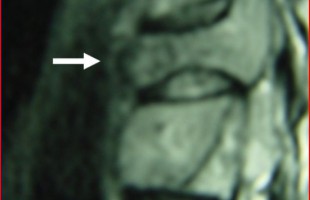

Η Μα. Φο. 26 ετών προ δεκαετίας υποβλήθηκε (αλλαχού) σε χειρουργική επέμβαση στη θωρακο-οσφυική περιοχή της σπονδυλικής στήλης (Σ.Σ.). Η επέμβαση εγένετο προκειμένου να αφαιρεθεί καλοήθης νεοπλασματική εξεργασία (επενδύμωμα) η οποία της είχε προκαλέσει σφιγκτηριακές και νευρολογικές διαταραχές στα κάτω άκρα. Προκειμένου να γίνει εξαίρεση της νεοπλασματικής βλάβης, πραγματοποιήθηκε ευρεία αφαίρεση οπίσθιων στηρικτικών στοιχείων τωνRead more →